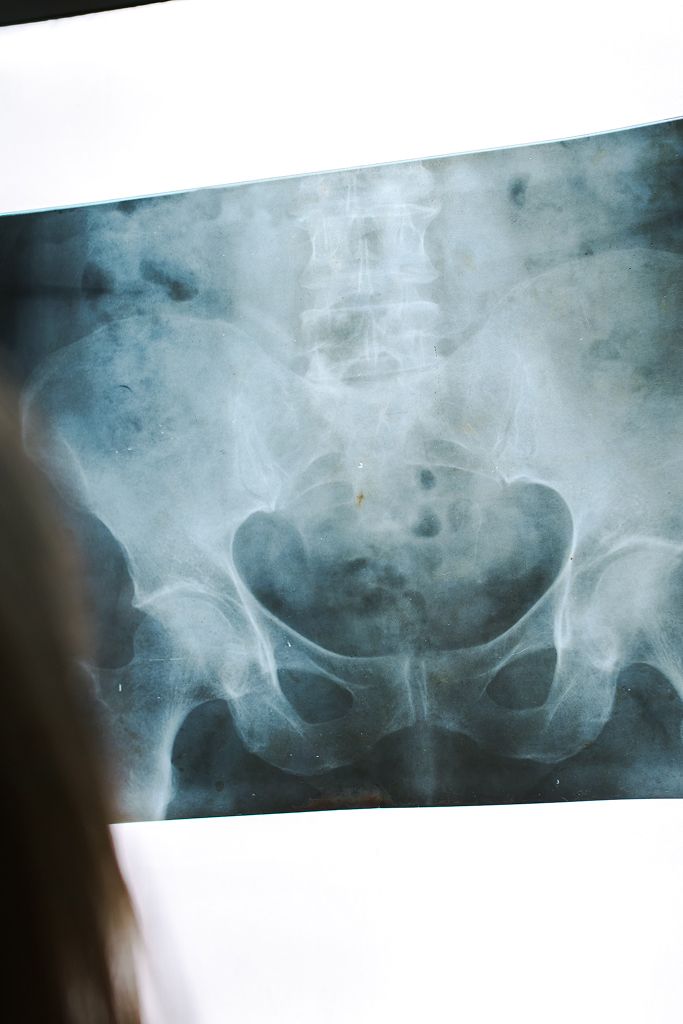

What is Pelvic Trauma?

Types of Pelvic Trauma

Stable Pelvic Fracture

Unstable Pelvic Fracture

Open Pelvic Fracture

Acetabular Fracture